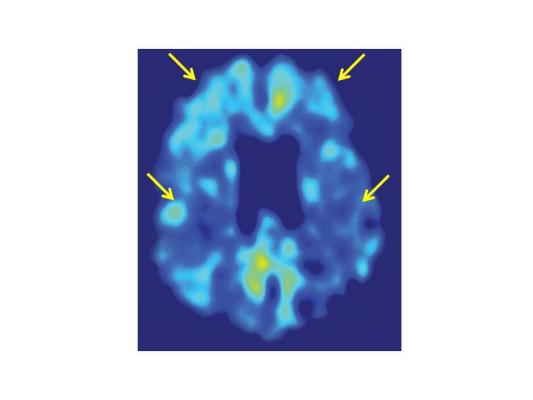

As expected, the team found that performing this task 30 minutes a day for several weeks after injury resulted in greatly improved motor function. To estimate changes in brain activity associated with the recovery, they imaged the regional brain activity using H215O-positron emission tomography (PET) before injury and at the early and late stages of recovery while monkeys performed the task. They found that activity in the ventral premotor cortex — a brain region somewhat distant from the injury — was higher during the early stage of recovery than before the injury. They also conducted what is known as a psychophysiological interactions (PPI) analysis and found that when monkeys performed the task in the later stages of recovery, connections between the lesion site and regions of primary motor cortex immediately surrounding it became stronger.